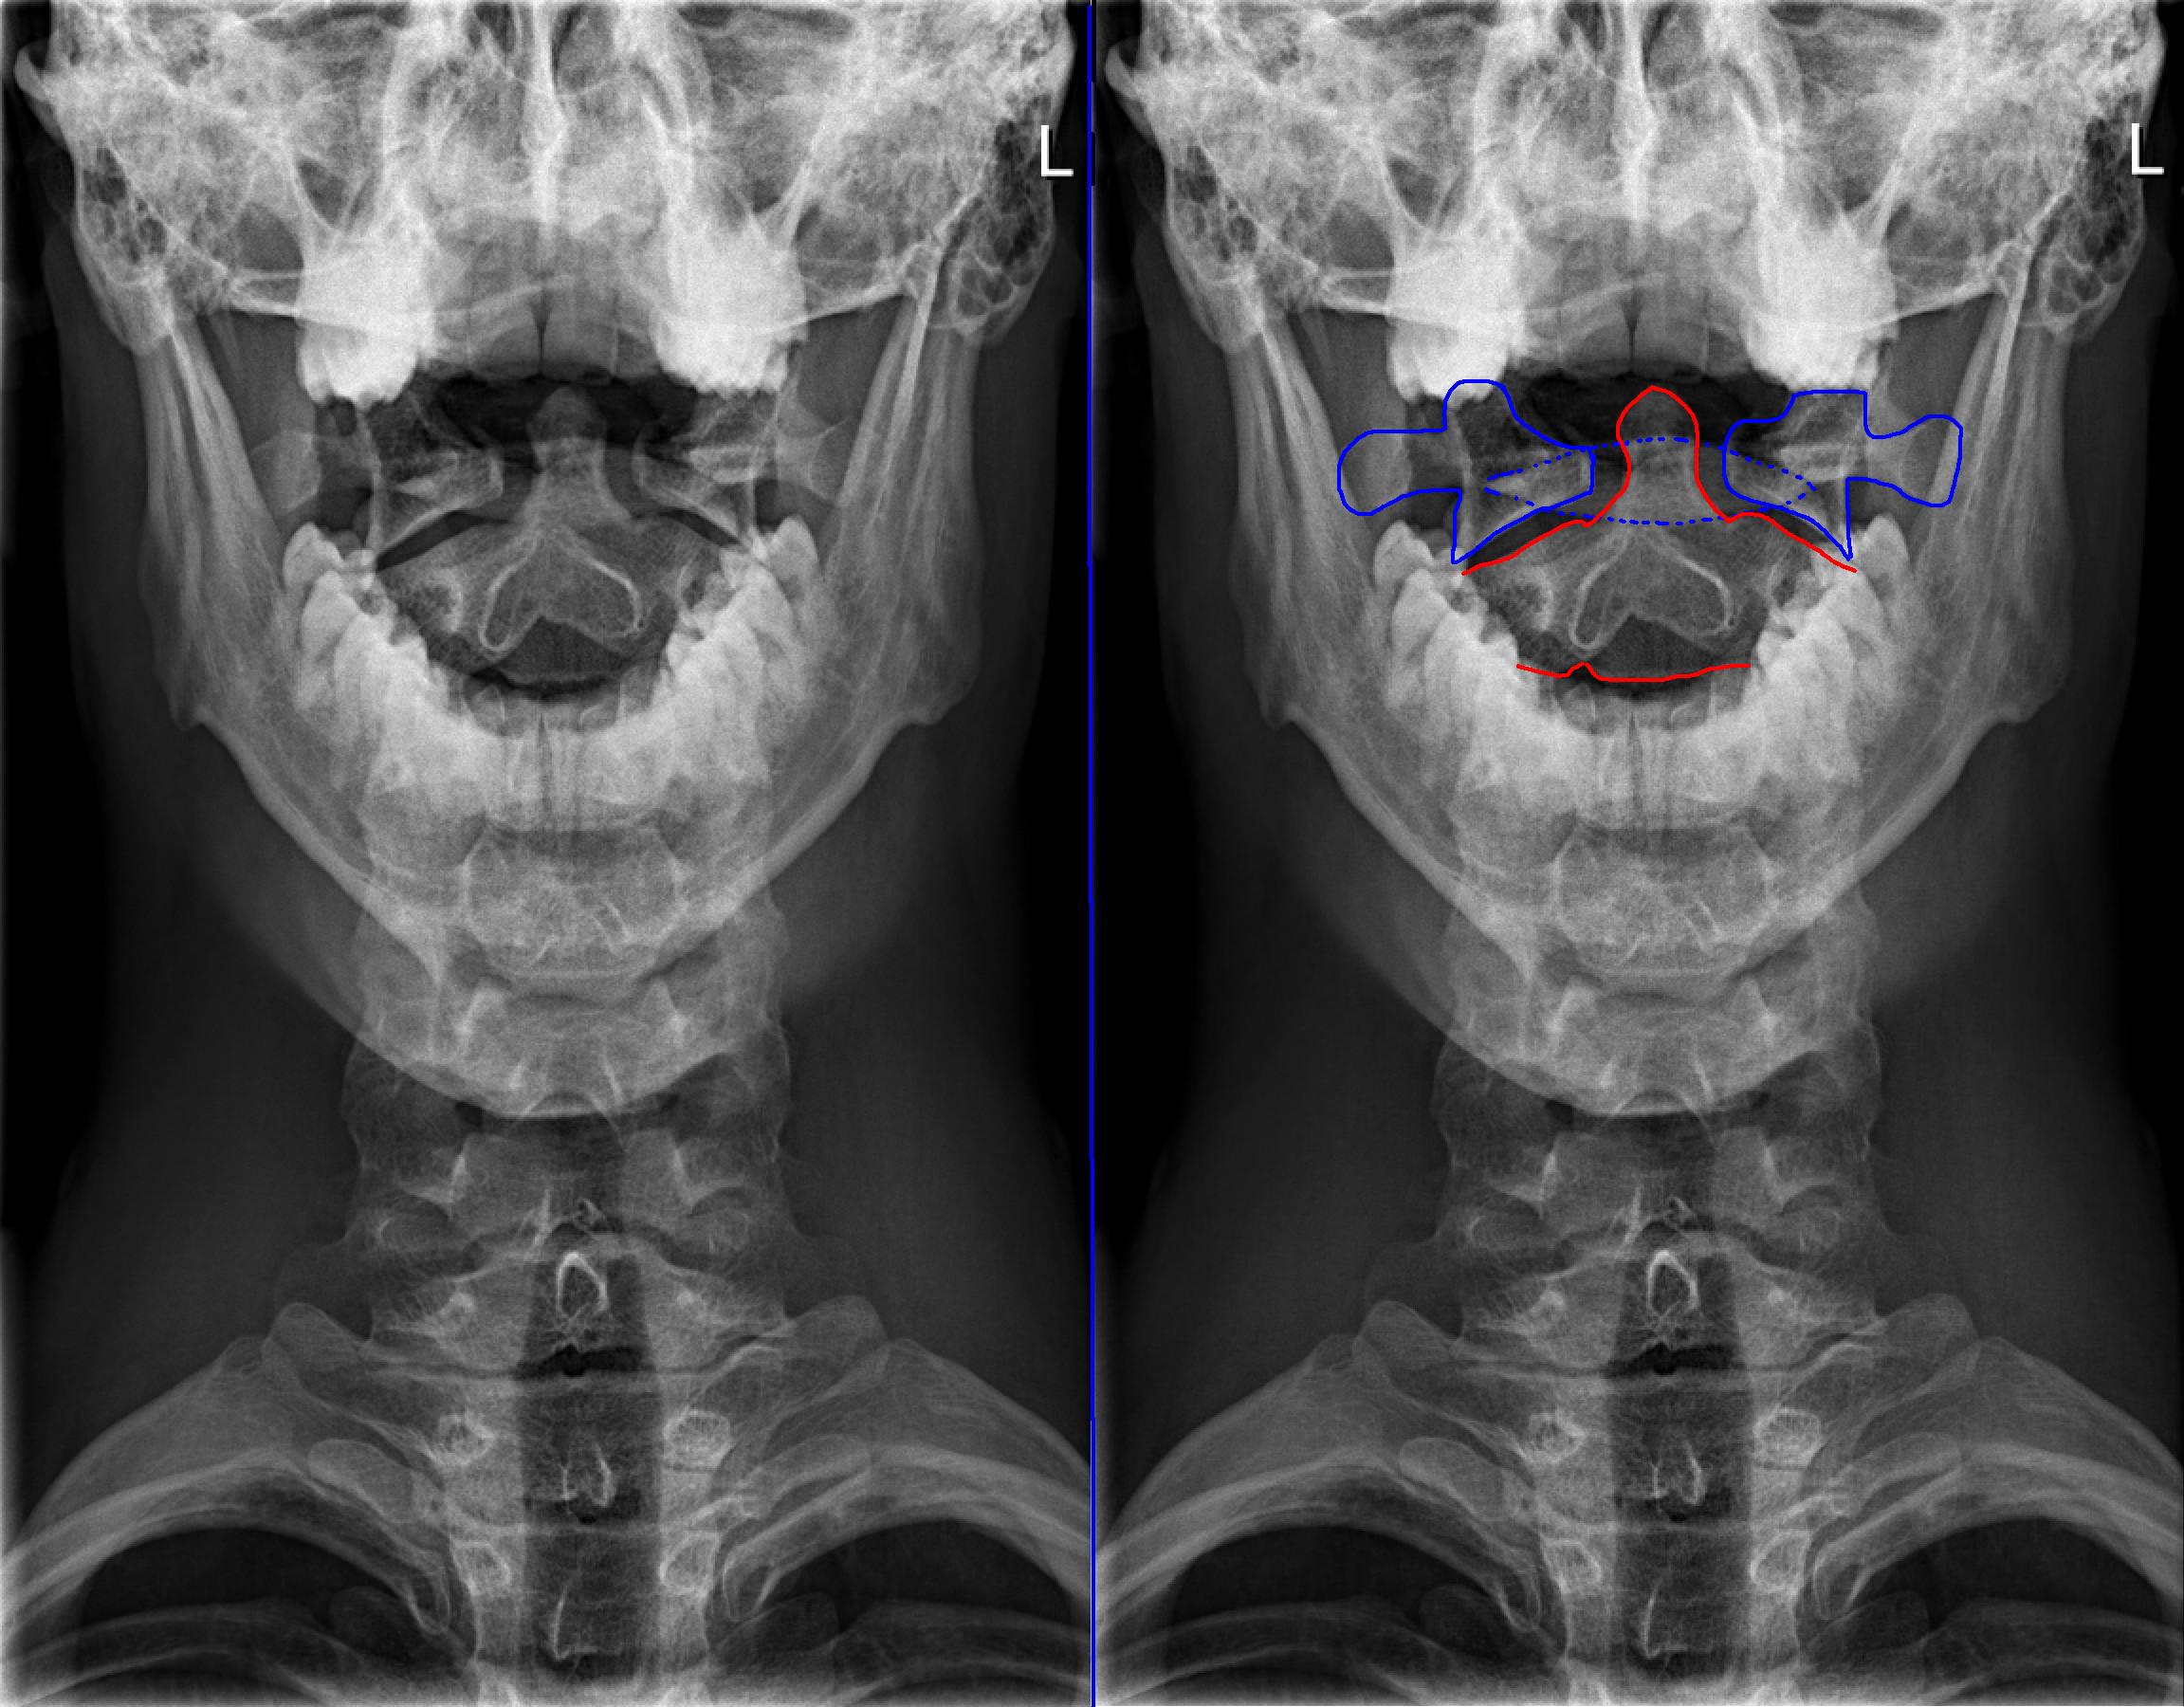

Der atlaswirbel ist der erste halswirbel, der zusammen mit dem zweiten halswirbel (axis) die verbindung zwischen kopf und wirbelsäule darstellt.

Atlaswirbel englisch | atlaswirbel translation. Eine therapie des atlaswirbels korrigiert beschwerden, die mit dem atlasgelenk im zusammenhang stehen. Der atlaswirbel wurde nach dem griechischen titanen benannt, der von zeus bestraft wurde, die welt und den himmel für eine ewigkeit auf seinen schultern zu tragen. Die atlaswirbel verbinden köpfchen und leib. Sitzen die kontaktflächen zwischen atlaswirbel und kopf nicht gleichmäßig aufeinander, kann dies zu einer problematik führen, die im volksmund oft als „atlasblockade bezeichnet wird und. Heute geht es um den atlaswirbel. Der atlaswirbel ist der erste halswirbel, der zusammen mit dem zweiten halswirbel (axis) die verbindung zwischen kopf und wirbelsäule darstellt. Heute geht es um den atlaswirbel. Der atlaswirbel ist der oberste halswirbel und stützt den kopf. Man hört sehr viel über atlaskorrekturen und schmerzen im nackenbereich. Schau dir unsere auswahl an atlaswirbel an, um die tollsten einzigartigen oder spezialgefertigten, handgemachten stücke aus unseren shops zu finden. Первый шейный позвонок (andrey truhachev). Atlaswirbel übungen für das atlasgelenk kann man hier im video und in der bildfolge sehen.